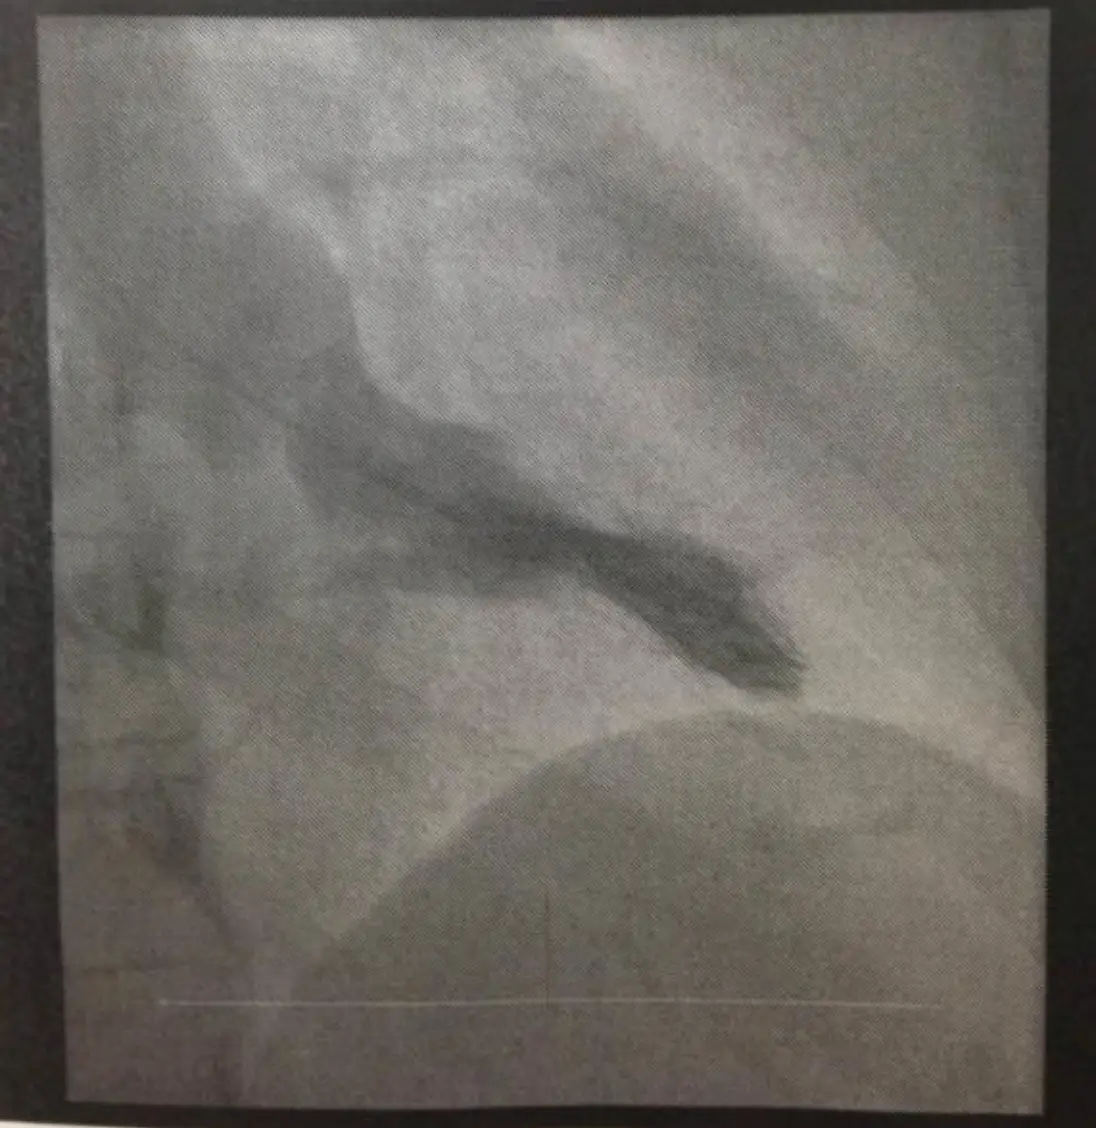

病人64歲家庭主婦,近三個月來有間歇性胸悶及運動性呼吸困難。病人有氣喘及高血壓10年病史,規則 服用Ipratropium或Furosemide + Aldactone + Digoxin + Aspirin。事實上病人過去10年前就有類似症 狀,再多加服用上列藥物,也就改善。只是近月來全身倦怠,食慾不振,上腹微痛及體重減輕七公斤,乃 於七月廿六日住院診療。病人Height: 156 cm Weight: 68kg ; T/P/R:37.1/88/16;。 BP: 110/73 mmHg。理學檢查發現心臟大小正常,規則律跳,唯心尖處(Apical area) 有雙峰脈波bifid pulse) 及在左上 胸緣及心尖處有Gr 4/6 Pansystolic murmur,下肢有2度浮腫,但其他器官並未有異常。血球檢 查:WBC,10.14k/uL; RBC, 4.79 M/uL; Platelet, 169K/uL。血液生化結果: Albumin, 4.2 gm/dL; T-Bil, 0.86 mg/dL; BUN, 16.8 mg/dL; Cre1.0 mg/dL; ALT, 90 U/L。其心電圖及胸部X光如圖。經心導管檢查: 大動脈 血壓, 142/68 mmHg; 左心室出口部( LVOT), 158/28 mmHg; 左心室心尖部, 198/32 mmHg. 其左心室造影 及Cardiac CT如圖。請問病人的正確心臟診斷是: 圖片描述 圖片描述 圖片描述 圖片描述

3. 左心室造影

– 顯示典型「hourglass」中腔狹縮:心室中部劇烈狹窄,下方心尖腔持續存在,形成雙腔構造。

– 心尖部明顯擴張、牆面動作遲緩或無動作,符合心尖動脈瘤定義。